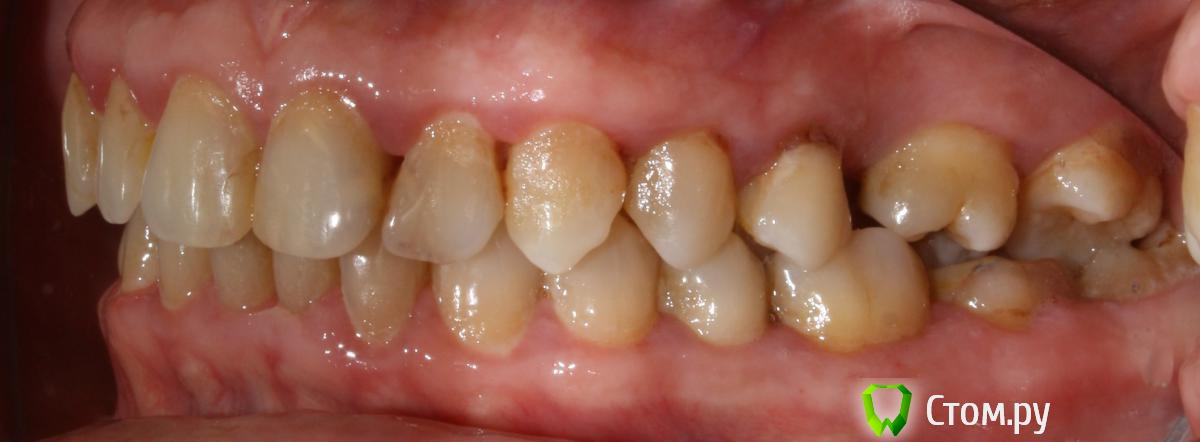

artem29 Опубликовано 12 декабря, 2013 Поделиться Опубликовано 12 декабря, 2013 всем привет!!! Я хирург. В клинике планируется работа с микровинтами. Пациентка брекетсистему "носить" не планирует (остановились на локальном решении задач) Задача: Ортопеду необходимо освободить место для будущих искусственных зубов 1.6 и 3.6. Для этого пациентка (50 лет), отправляется на консультацию к ортодонту для решения вопроса у дистализации зубов 1.7 и 3.7. В данном клиническом случае по хирургическим показаниям зубы мудрости планировались на удаление, сейчас добавились и ортодонтические, как я понимаю для дистализации 1.7 и 3.7 надо удалить 1.8 и 3.8. Ортодонт на микровинтах не работала, но мотивация есть. С ортодонтом видемся редко, у нас в клинике только консультативны прием, обсудить что-то вместе крайне редко получается (тем более провести совместную консультацию), меня как хирурга ортопед попросил посмотреть снимки, определить свой (хирургический объем работы). Изучив информацию (литературу и форумы) я пришел к такому варианту действий,чтобы дистализировать 1.7 необходимо удалить 1.8 установить микровинт вестибулярно между корнями 1.4 и 1.3 (т.к. там больше места чем между 1.5 и 1.4) к 1.7 фиксировать брекет-замок, между ними установить пружину, зуб 1.7 дистализируется. для дистализации 3.7 необходимо удалить 3.8, оценить состояние костной ткани, возможно установить микровинт дистально одномоментно с удалением 3.8 если межокклюзионной высоты для головки микровинта будет достаточно. Вторым путем (при отсутствии состоятельной костной опоры в момент удаления 3.8 является установка микровинта между корнями зубов 3.4 и 3.5, брекет на зуба 3.7 + пружина. есть ещё один вариант. удалить 1.8 и 3.8, дождаться пока пройдет формирование костной ткани (сделать КТ через 3 месяца) установить микровинты в уже сформированную кость Вопросы: 1. кто определяет место установки микровинтов, ортодонт или хирург? 2. если изначально определяет место установки винтов хирург, то какие зоны необходимо в данной случае взять за костные опоры (куда ставить установить микровинты) к какие ортодонтические конструкции будут? 3. оптимально ли в данной ситуации дистализировать с помощью микровинтов, или возможны другие варианты Ссылка на комментарий

M@estro Опубликовано 12 декабря, 2013 Поделиться Опубликовано 12 декабря, 2013 Интрузию 4.6 и 2.6 я просить бы не стал. (а 2.6 вообще под вопросом на выход). Думаю, дистализацию в первом квадранте можно выполнить "пружинкой" ,оттолкнувшись от премоляров,хотя утверждать не берусь. P.s. Гигиена - кошмар. Ссылка на комментарий